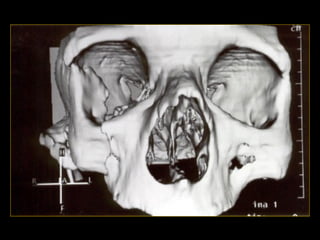

10%NORMAL Valoración clínica No hay deformidad palpable Domicilio Deformidadpalpable o herida penetrante Cráneo simple TAC, si la fx cruza ramas de la meníngea media Sospecha Fx base Estudio simple proyecciones para base Examen neurológico anormal Sospecha de lesión TAC 60% Agresiones 17% Acc. Autom Otras

I. Pasa através de la porción media del maxilar superior II. Piramidal, cruza al etmoides oblicuamente. III. Supracigomatica, comienza en la zona nasal con extension al etmoides.

• 38.